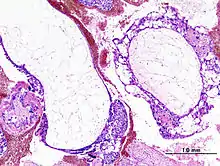

Histopathologic image of hydatidiform mole (complete type). H & E stain.